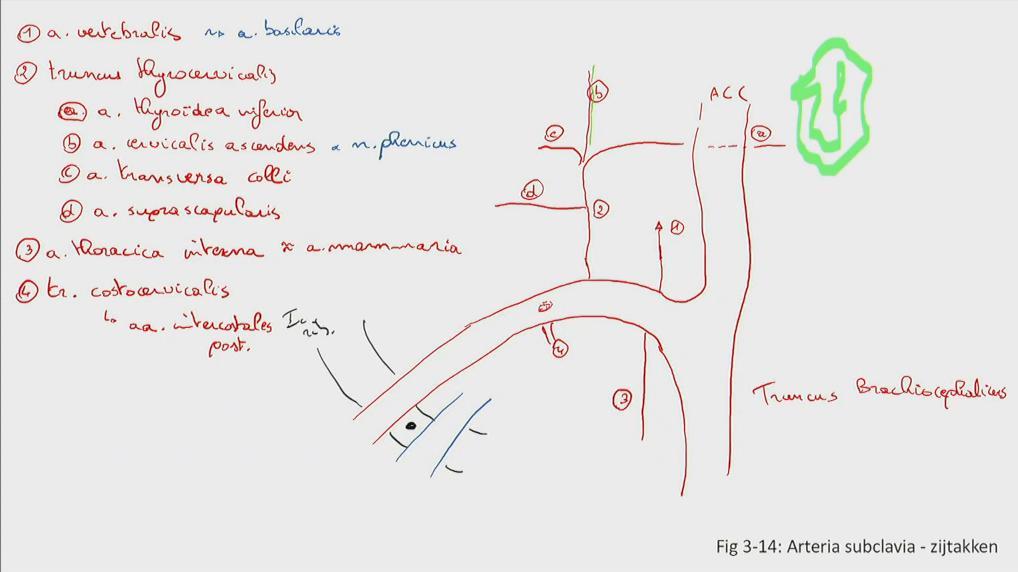

Fig 3.14: a. subclavia - zijtakken

glandula thyroidea = schildklier (groen) rib I tuberculum m. scalenus anterior v subclavia dextra -

truncus brachiocephalicus

a carotis communis (ACC) -

a subclavia dextra

a vertebralis (naar foramen transversarium C6-C2, a. basilaris) -

truncus thyrocervicalis

a thoracica interna = a. mammaria (langs sternum) -

truncus costocervicalis (posterieur)

|